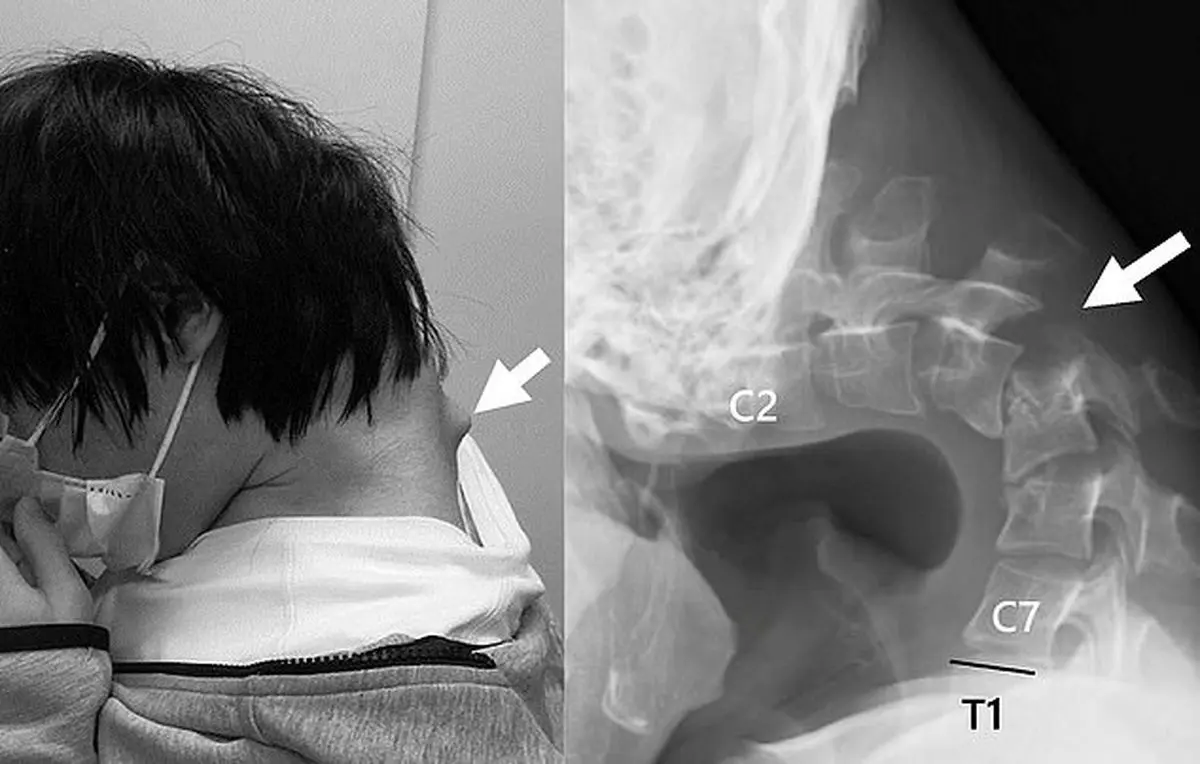

بر اساس این گزارش، این جوان ۲۵ ساله ژاپنی، که به بازی‌های ویدیویی روی تلفن هوشمند خود اعتیاد پیدا کرده بود، پنج ساعت مداوم با سر پایین به بازی مشغول بود و در نتیجه به بیماری نادری به نام «سندرم سر افتاده» (Dropped Head Syndrome ) مبتلا شد. این بیماری به دلیل پایین نگه داشتن سر برای مدت طولانی ایجاد شده است.

در این گزارش تصاویری که نشان می‌دهد چگونه گذراندن ساعت‌ها برای بازی با تلفن هوشمند می‌تواند به «سندرم سر افتاده» ترسناک منجر شود، و باعث خمیدگی مزمن و دائمی فرد در طول عمر خواهد شد، منتشر شده است.

به گفته امدادگران ژاپنی، گردن این جوان ۲۵ ساله به دلیل بازی مداوم با تلفن همراه به شدت ضعیف شده بود، به طوری که دیگر نمی‌توانست سر خود را بالا نگه دارد.

تصاویر برآمدگی قابل توجهی در گردن این جوان نشان می‌داد که به گفته امدادگران به خاطر «کشیدگی بیش از حد مهره‌ها» به وجود آمده است.